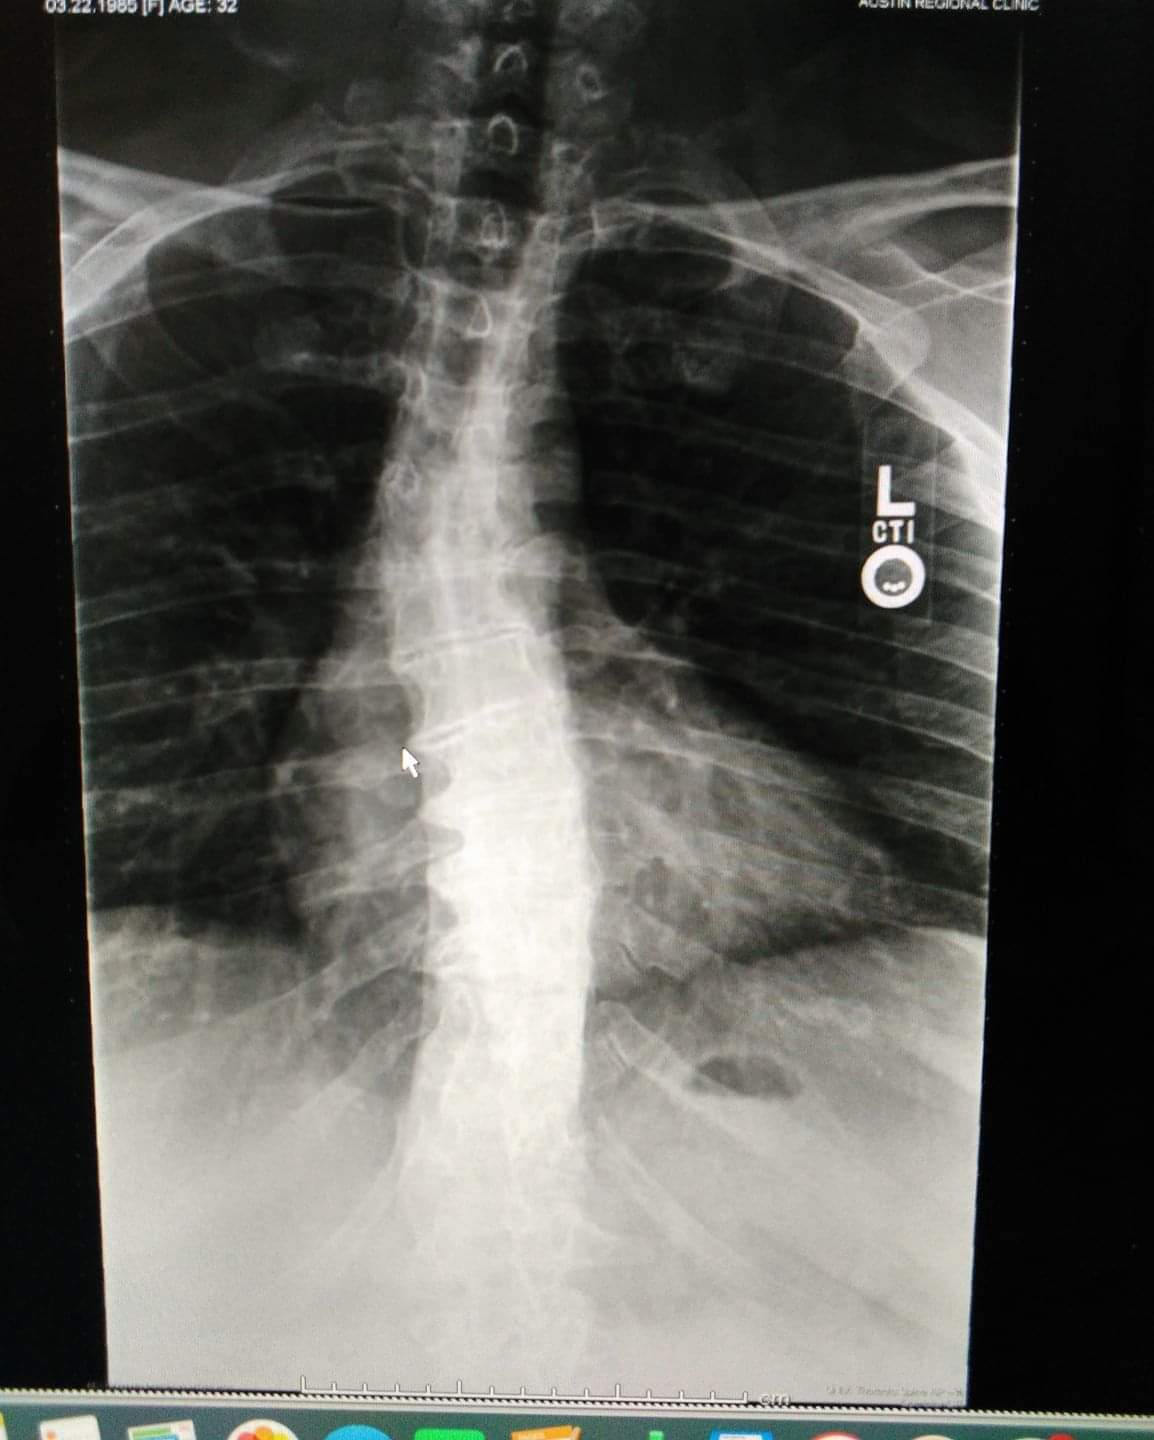

From www.researchgate.net

Xray shows degenerative scoliosis in lumbar spine. Download Scientific Diagram Scoliosis Caused By Degenerative Disc Disease Adult scoliosis, where the spine curves. Degenerative disc disease (ddd) and scoliosis are two distinct conditions that can affect the spine, sometimes. Degenerative scoliosis, prevalent in the elderly due to aging and arthritis, emerges from the gradual degeneration of disc and facet. This contact can cause pain and other problems, such as: Degenerative scoliosis is an abnormal spinal curve caused. Scoliosis Caused By Degenerative Disc Disease.